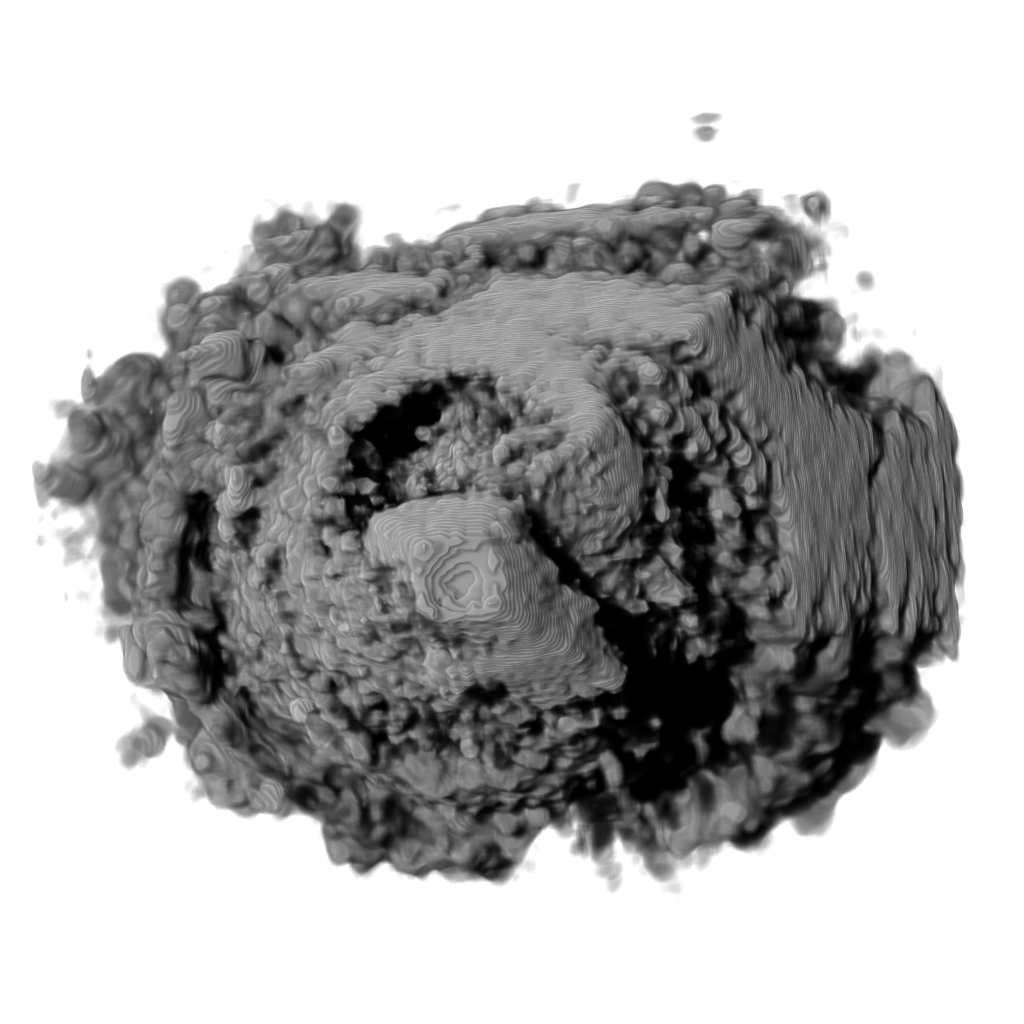

Recent works show that global illumination models based on gradient-free methods are suitable for rendering ultrasound volumes Ropinski10 ; solteszova10 . Ropinski et al. described a volumetric lighting model which simulates scattering and shadowing Ropinski10 . They use slice-based volume rendering from the view of the light source to calculate a light volume and raycasting to render the final image (see Figure 7b). A perceptual evaluation of the generated images indicates, that the proposed model yields stronger depth cues than gradient-based shading. Šoltészová et al. presented a single-pass method for simulation of light scattering in volumes solteszova10 . Light transport is approximated using a tilted cone-shaped function which leaves elliptic footprints in the opacity buffer during slice-based volume rendering. They use a slice-based renderer with an additional opacity buffer. This buffer is incrementally blurred with an elliptical kernel, and the algorithm generates a high-quality soft-shadowing effect (see Figure 7c). The light position and direction can be interactively modified. While these two techniques have been explicitly applied to 3D US data, the application of other volumetric illumination models potentially also improves the visual interpretation of 3D US data. Figure 8 shows a comparison of six different shading techniques as applied to a 3D US scan of a human heart. While the first row of Figure 8 shows examples for the already addressed shading techniques, the second row shows three alternative approaches. Figure 8d incorporates scattering of light in volume data, as proposed by Kniss et al. kniss02halfangle . Their slicing technique allows textured slices to be rendered from both light and viewing direction simultaneously. By sampling the incident light from multiple directions while updating the light’s attenuation map, they account for scattering effects in slice-based volume rendering. Figure 8e shows the application of the directional occlusion shading technique schott09directionalocclusion . This technique constrain the light source position to coincide with the view point. Finally, Figure 8f shows the application of a technique based on spherical harmonic lighting lindemann10materials .